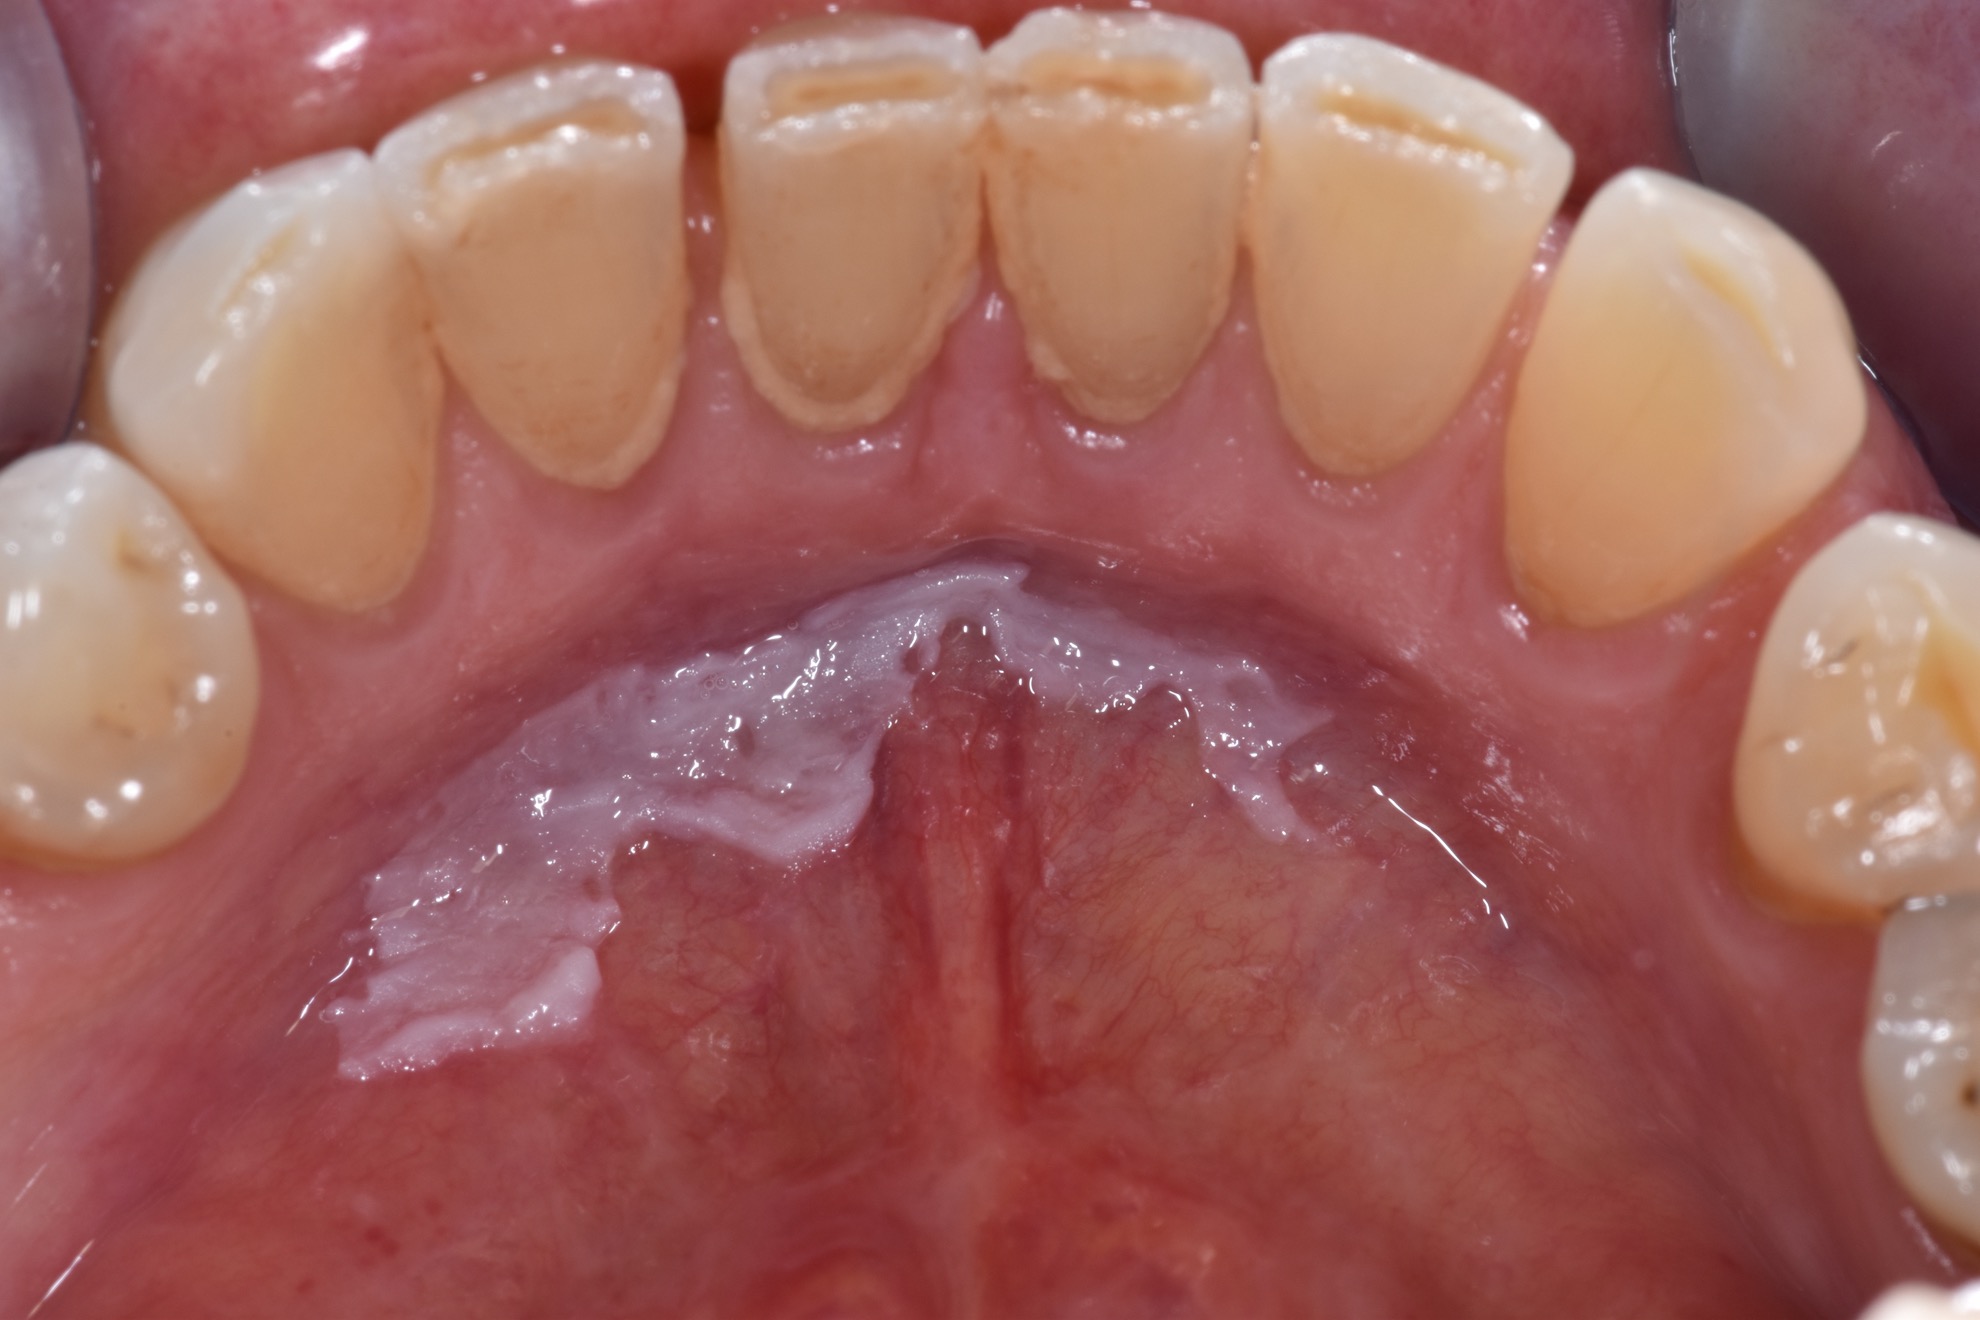

White Spots On Gums Leukoplakia . Leukoplakia is a condition involving thickened white patches on the mucous membranes (lining) of the mouth, gums, and/or. Leukoplakia patches on your tongue, gums, roof of your mouth, or the inside of your cheeks may be: If you accidentally bite the inside of your cheek or burn the roof of your. The patches don’t hurt but they don’t. They may thicken or harden overtime, and they. They are typically harmless, although some doctors think they are precancerous. Leukoplakia describes white patches on the roof of the mouth, tongue, and gums. This mouth condition appears as thick, white patches on the gums, the cheeks and the bottom of the mouth that cannot be scraped. Leukoplakia are small white patches that appear on the gums, the insides of the cheeks, the bottom of the mouth, and the tongue. Leukoplakia is a condition that creates white patches on your tongue, gums or the inside of your cheeks. But not every white patch in the mouth is leukoplakia.

If you accidentally bite the inside of your cheek or burn the roof of your. Leukoplakia describes white patches on the roof of the mouth, tongue, and gums. They may thicken or harden overtime, and they. They are typically harmless, although some doctors think they are precancerous. But not every white patch in the mouth is leukoplakia. Leukoplakia are small white patches that appear on the gums, the insides of the cheeks, the bottom of the mouth, and the tongue. The patches don’t hurt but they don’t. Leukoplakia is a condition involving thickened white patches on the mucous membranes (lining) of the mouth, gums, and/or. This mouth condition appears as thick, white patches on the gums, the cheeks and the bottom of the mouth that cannot be scraped. Leukoplakia is a condition that creates white patches on your tongue, gums or the inside of your cheeks.

White Spots On Gums Leukoplakia Leukoplakia patches on your tongue, gums, roof of your mouth, or the inside of your cheeks may be: Leukoplakia patches on your tongue, gums, roof of your mouth, or the inside of your cheeks may be: This mouth condition appears as thick, white patches on the gums, the cheeks and the bottom of the mouth that cannot be scraped. If you accidentally bite the inside of your cheek or burn the roof of your. Leukoplakia describes white patches on the roof of the mouth, tongue, and gums. Leukoplakia are small white patches that appear on the gums, the insides of the cheeks, the bottom of the mouth, and the tongue. The patches don’t hurt but they don’t. But not every white patch in the mouth is leukoplakia. They may thicken or harden overtime, and they. They are typically harmless, although some doctors think they are precancerous. Leukoplakia is a condition involving thickened white patches on the mucous membranes (lining) of the mouth, gums, and/or. Leukoplakia is a condition that creates white patches on your tongue, gums or the inside of your cheeks.